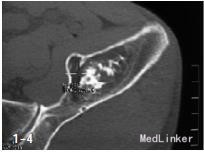

查体:左侧髋关节“4”字实验完成较右侧差,左下肢直腿抬高实验30°。 辅查:腰椎CT:L4/5、L5/S1腰椎间盘突出并左侧隐窝狭窄,相应神经根受压,行髋部X线检查提示左髂骨内占位,进一步行骨盆CT检查提示:左髂骨内可见1大小约4cm×3cm近椭圆形占位性病变,边界清楚,周围骨组织可见厚薄不一的硬化边,其中央有钙化表现,未见骨膜反应,测CT值在-118HU~-129HU之间

诊断:(1)左髂骨占位,脂肪瘤待查;内生软骨瘤待查。(2)腰椎间盘突出症(L 4/5、L5/S1)。 治疗:手术剔除。术中所见:左髂骨内可见1大小约4cm×3cm黄色软组织肿块,表面柔软,边界清楚,肿瘤内可见纤维间隔,中央部分不均匀钙化,与周围骨组织无浸润、骨质无破坏表现,术中诊断左髂骨内脂肪瘤。